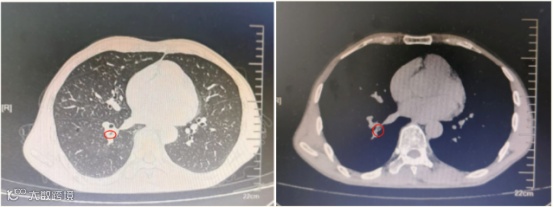

患者此前在耳鼻喉科的检查中并未发现上呼吸道异物,故接诊医生安排其至放射科行胸部CT进一步检查:

检查发现患者右下叶外后基底段有一块阴影(如下图),考虑异物存在。